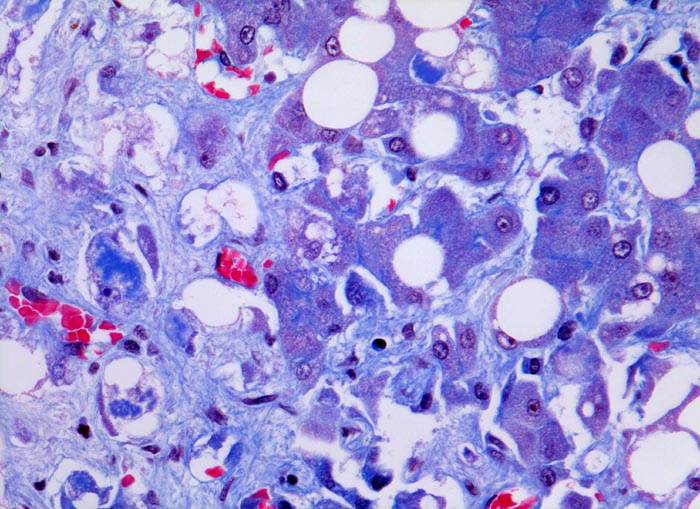

PathoPic – image database / PathoPic ID 4550 - aethylische Leberzirrhose: Mallory-Denk Körper und Steatose

aethylische Leberzirrhose: Mallory-Denk Körper und Steatose

An der Parenchym/Bindegewebsgrenze Hepatozyten mit intrazytoplasmatischen Mallory-Denk Körpern: Irregulär begrenzte, pfützenartige, hirschgeweihartige oder raupenförmige blaue Zytoplasmastrukturen. Andere Hepatozyten enthalten eine grosse Fettvakuole, welche den Kern zur Seite verdrängt (grobtropfige Verfettung). Vereinzelt ist eine feintropfige Verfettung nachweisbar mit multiplen intrazytoplasmatischen Fetttropfen.

Mallory Körper entsprechen intrazytoplasmatischen Ablagerungen von kollabiertem Zytoskelett (Intermediärfilamenten), das zusammen mit ubiquitinierten Proteinen wie Heat Shock Proteinen kondensiert. Sie finden sich in nicht verfetteten Hepatozyten und sind typischerweise hirschgeweihförmig. Immunhistochemisch färben sich die Mallory Körper mit Ubiquitin an. Vorkommen von Mallory Körpern bei alkoholischem Leberschaden, Autoimmunhepatitis, Cholestase, Medikamentös toxischem Leberschaden, hepatozellulärem Karzinom, nicht alkoholischer Steatohepatitis, PBC, PSC und Morbus Wilson.